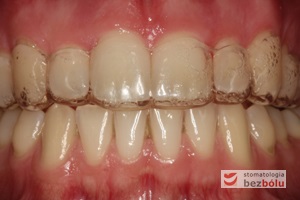

Młody 28-letni, pogodny, stale uśmiechnięty pacjent zgłosił się celem korekcji wad zębowych ograniczających pełną ekspresję uśmiechu. Głównym problemem był dodatkowy siekacz boczny (dwójka) po stronie prawej w łuku górnym. Dodatkowy ząb spowodował stłoczenia pozostałych zębów w łuku górnym oraz przesunięcie linii pośrodkowej. Obliczenia dostępnego miejsca dla siekacza bocznego wpłynęły na wybór zęba przeznaczonego do ekstrakcji. Usunięto dwójkę ustawioną dowargowo, zaś jej „siostrę bliźniaczkę” skierowaną w stronę podniebienia wprowadzono do łuku zębowego w drodze leczenia ortodontycznego. Problemem było szczelne zamknięcie szpary poekstrakcyjnej z powodu nadmiaru miejsca w kości. Wyrównano linię pośrodkową. Leczenie przeprowadzono jednym łukiem ortodontycznym górnym, dolny łuk zębowy nie wymagał założenia aparatu. Po zdjęciu zamków korekcję detali przeprowadzono z użyciem pozycjonera wykonanego w technice termoformingu. Stabilizację efektów leczenia zapewnił stały retainer klejony do powierzchni podniebiennych siekaczy górnych.